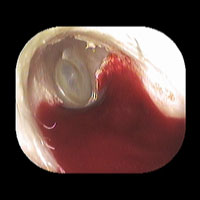

左真珠腫性中耳炎

左耳に白い真珠腫がみられます。外耳道から真珠腫をできる限り摘出しました。CTを撮影し、根治的な手術が必要でしたので、総合病院耳鼻咽喉科にご紹介し全身麻酔下に手術を行いました。

外耳道から清掃した後